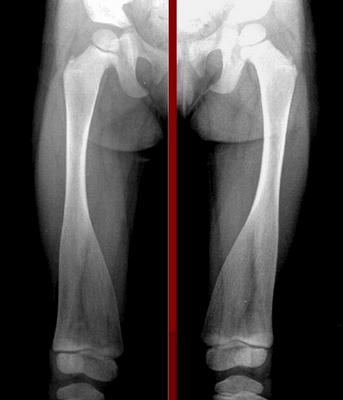

При диагностике врачи обращают внимание на характерное поражение проксимального отдела шейки бедра. Кости имеют неправильную форму, недостаточную плотность, низкое содержание кальция и микроэлементов. На рентгеновских снимках заметны неровные контуры, расширенные участки эпифизов.

Для пациентов с типом MакКьюзика характерны хроническая анемия, патологии кишечника. На рентгеновских снимках заметно увеличение метафизов в области коленного сустава. В детском возрасте нередко встречается двояковыпуклое строение позвонков, которое постепенно исчезает после взросления.